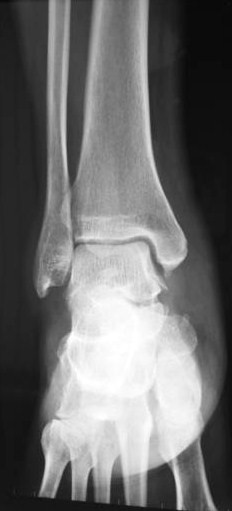

For example, this sportsman presented with persistent pain in the anteromedial aspect of his right ankle after an inversion sprain which happened 4 months ago.

X-ray of the right ankle appeared normal.